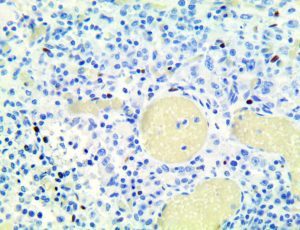

It is the ICU physician who is most likely to witness one of the deadliest manifestations of the abnormal immunological response, the cytokine storm syndrome (CSS). This response is also referred to by some as the cytokine release syndrome (CRS). CSS is characterized by continuous activation and expansion of macrophage and lymphocyte populations, which secrete large amounts of cytokines, causing the cytokine storm. This massive cytokine release is akin to hemophagocytic lymphohistiocytosis (HLH) disease, a syndrome characterized by initial unchecked and persistent activation of cytotoxic T lymphocytes and NK cells.

Clinical and laboratory manifestations of HLH include fever, enlarged liver and/or spleen, neurologic dysfunction, coagulopathy, liver dysfunction, cytopenias (i.e., low levels of erythrocytes, leukocytes, and/or platelets), hypertriglyceridemia, hyperferritinemia, hemophagocytosis, and eventually diminished NK cell activity as the immune system becomes progressively paralyzed. HLH can be familial (primary HLH) or secondary to another disease process (sHLH), such as rheumatic disease, in which it is referred to as macrophage activation syndrome (MAS, characterized by elevated ferritin).